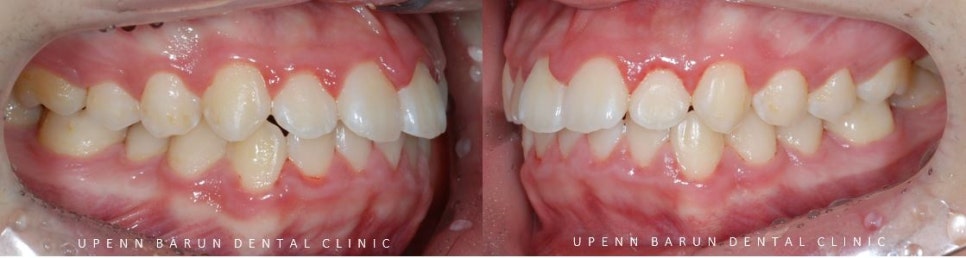

교정 전

사진에서 보시는 것처럼 윗니와 아랫니 사이에

꽤나 큰 공간이 관찰되었습니다.

악궁이 좁아 삐뚤빼뚤했던 치아들이

교정 후

발치된 공간으로 치아들이 올바르게 배열되며

교정치료가 만족스럽게 잘 마무리 되었습니다.

교정치료가 끝난 후의 사진을 보시면

교정치료 전과는 다르게

도드라져 보이던 앞니의 치열과 치축이 개선되면서

가지런하게 정리되고 예쁜 스마일로

바뀐 모습을 볼 수 있습니다. ^^**